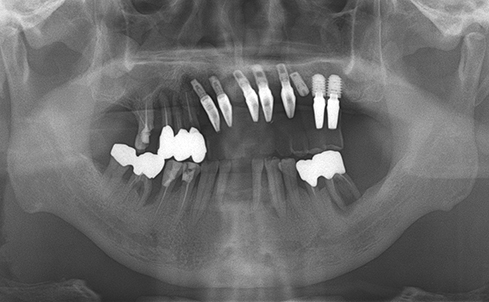

Implants/Bone Grafting

Fully edentulous clinical cases